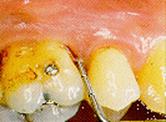

Código

2: presencia de tártaro y/o obturaciones defectuosas.